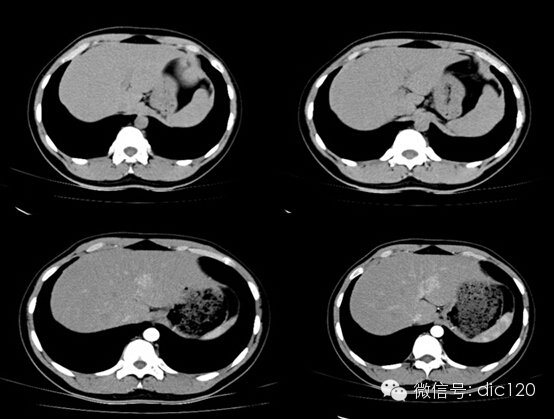

• 肝局灶性結(jié)節(jié)增生(FNH)

肝局灶性結(jié)節(jié)增生(FNH)

男,21Y,門診患者,病史不詳影像表現(xiàn):CT平掃與正常肝組織呈等密度,密度均勻,動脈期病灶快速明顯均勻強化,中心見小片狀低密度影(瘢痕),門脈期及延遲期對比劑快速退出呈等密度,中央低密度影延遲強化。MRI腫塊T2WI為稍高信號,中央高信號。動態(tài)增強掃描動脈期均顯著增強,門脈期輕度增強,延遲期瘢痕強化。

隨訪外院手術(shù)病理:肝FNH。

鑒別診斷:1、肝血管瘤:增